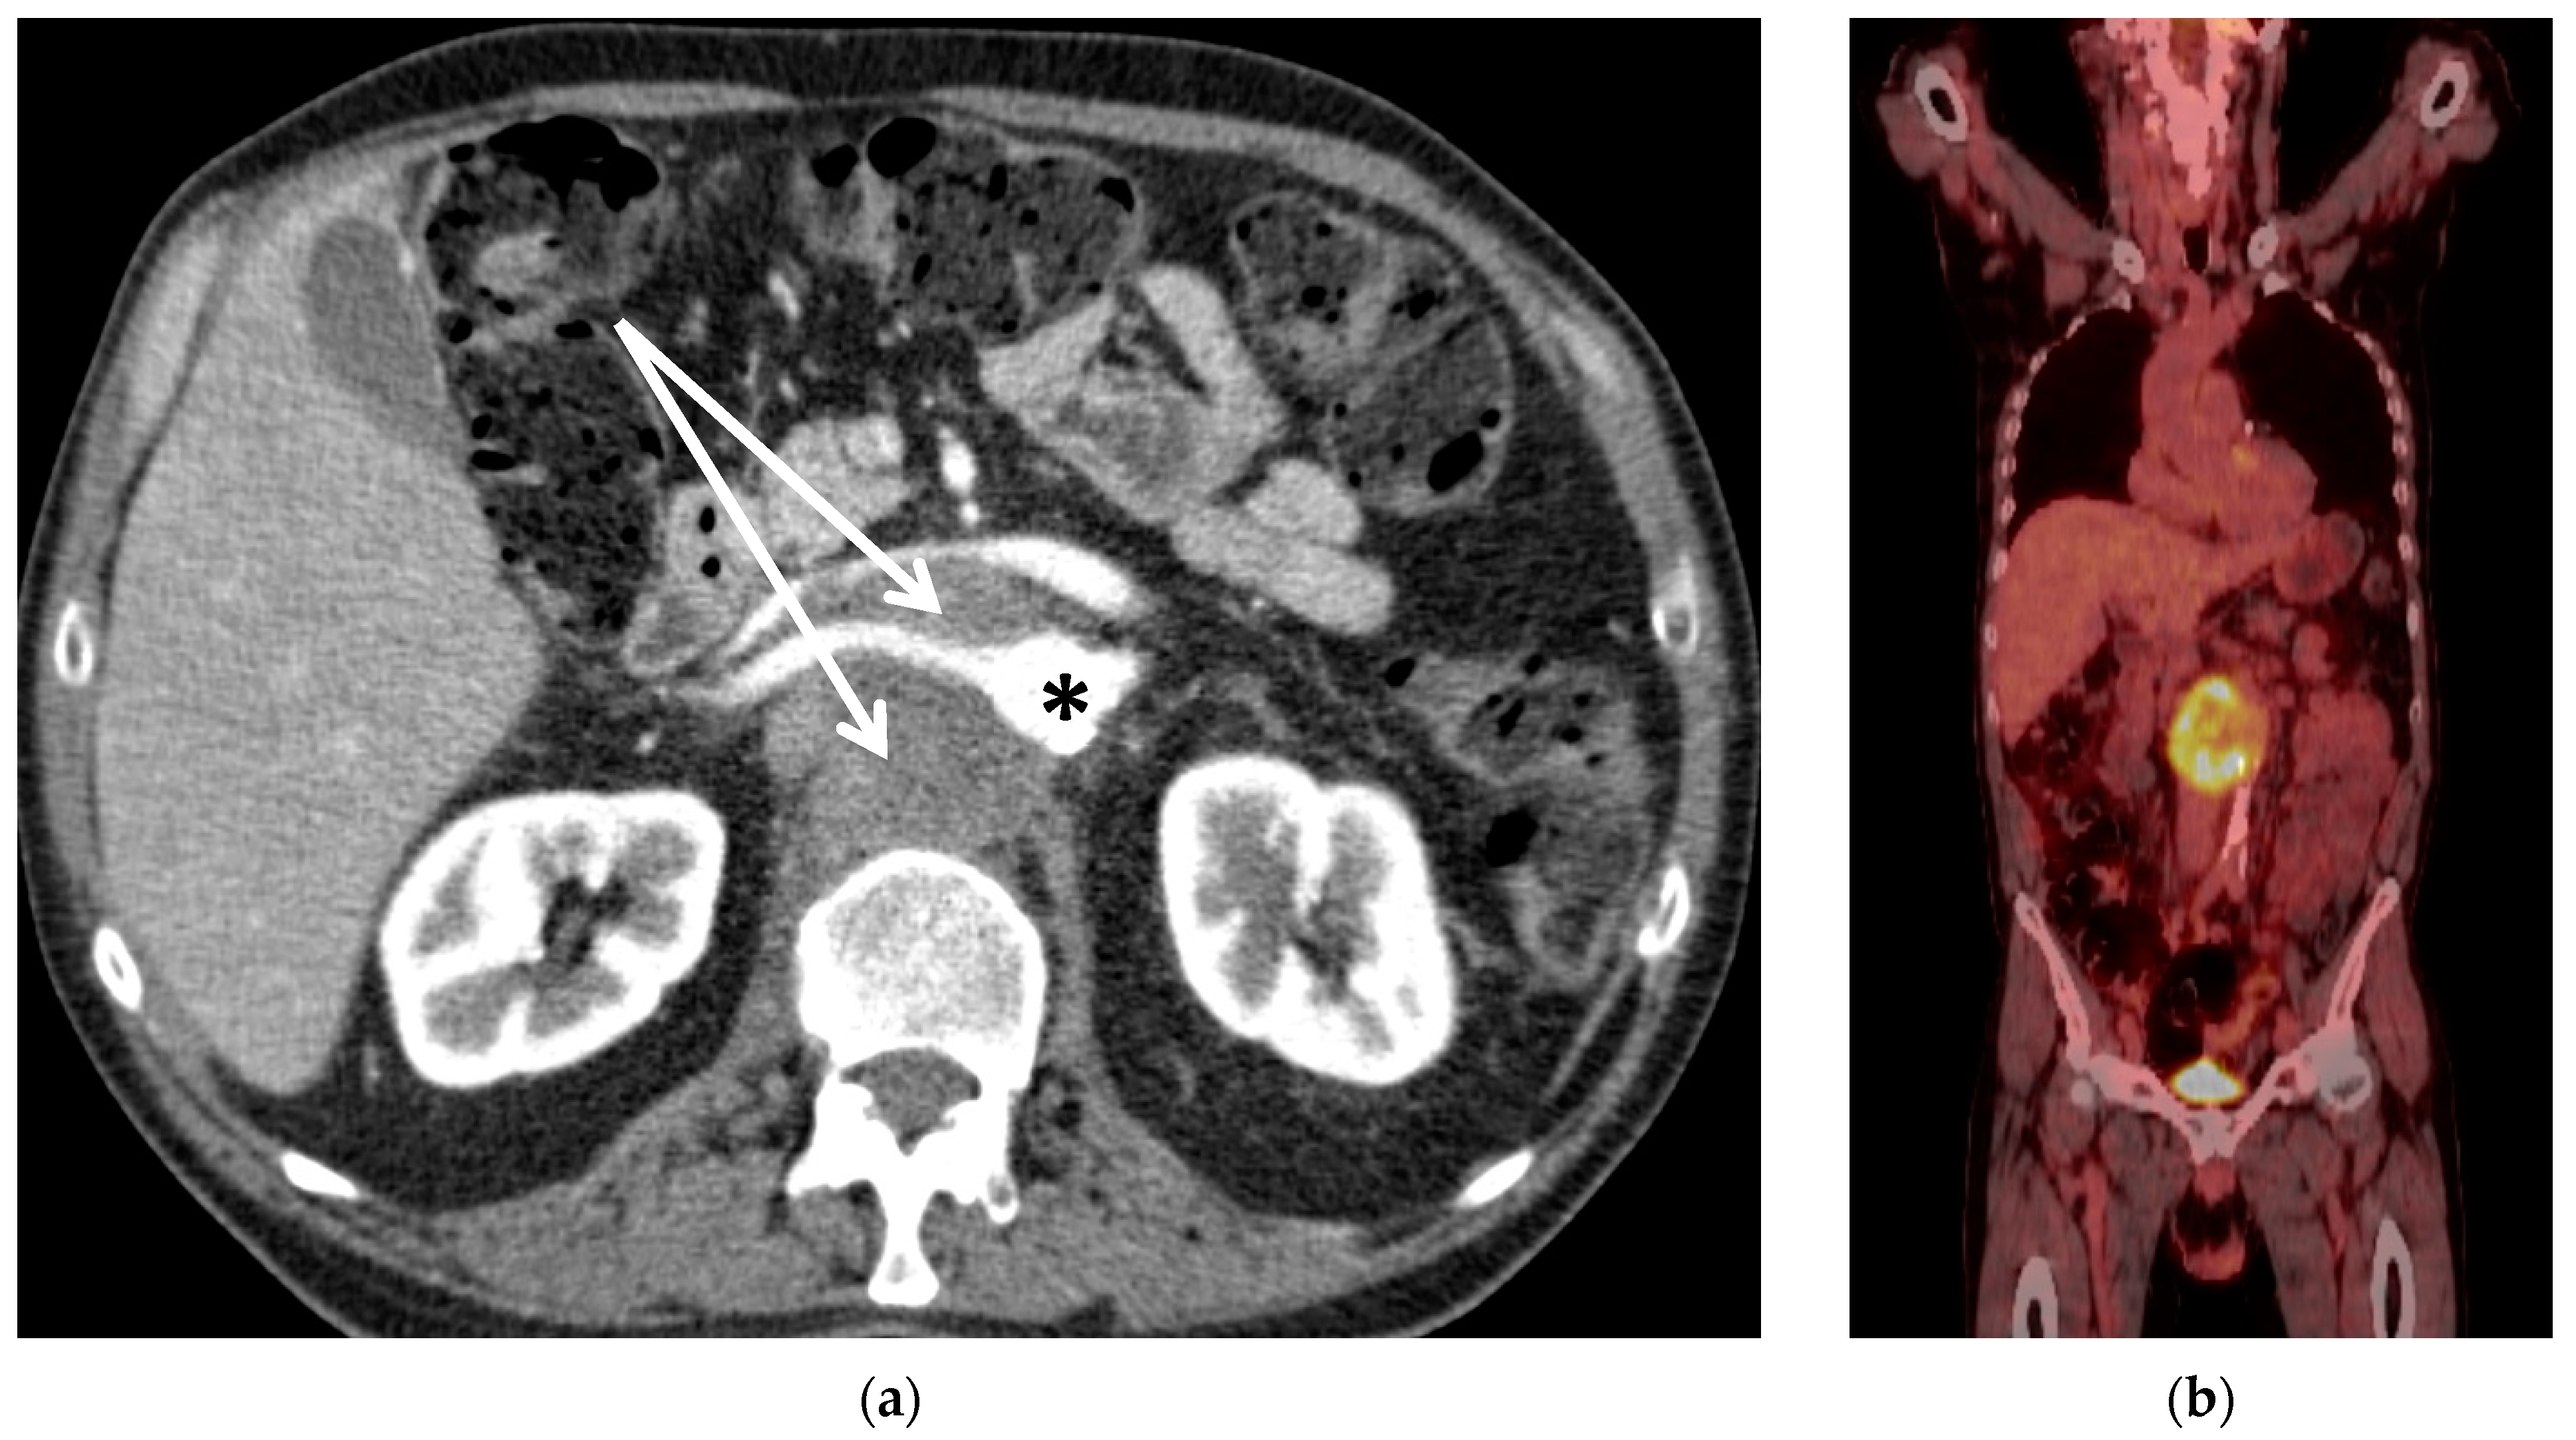

| 2 | m | 28 | Retro-peritoneal pleomorphic carcinoma | Compression of abdominal organs; bowel obstruction and hydronephrosis | Yes (50 Gy) | Yes | 0 | II |

| 3 | m | 56 | Chordoma L1 | Spinal compression with impending paraplegia | Yes, proton therapy (50 Gy) | No | 1 | I |